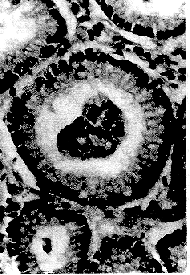

2.1.1 形成规则的套管。由单列上皮细胞组成,呈整齐的环状排列。此种套管的大多数,其上皮细胞极性同它们所在的主腺体上皮细胞是一致的(图1),只有少数套管的细胞与主腺体上皮相对而立(图2)。

图1 规则的套管,单列细胞整齐排列成

环状,极性与主腺体上皮一致(×400)

图2 规则的套管,套管上皮细胞与主腺体上皮

相对而立,无纤维血管轴心(×400)

以上两型套管内均空虚无物,或仅有少许粘液。注意到上皮细胞与主腺体上皮相向而立的套管中心并不存在纤维血管轴心。